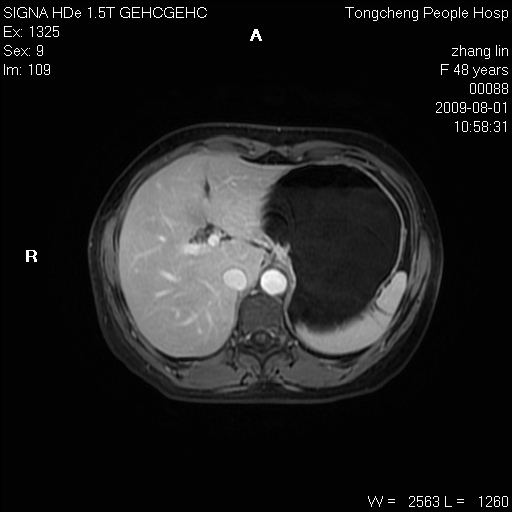

女,48岁。健康体检,彩超发现右肾占位性病变。平素健康。

临床诊断:右肾占位性病变,性质待定(囊肿?肿瘤?)。

上中腹部mr平扫+增强扫描,图像如下:

右肾上极见一类圆形病灶,t1wi呈等信号t2wi呈等高混杂信号,三期增强无强化,边界清---考虑囊肿出血。

同反相位均表现为等信号,病变无强化,考虑含蛋白的囊肿可能,弥散加权相或许有些帮助,